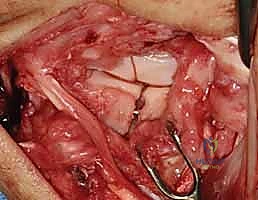

4. Lunotriquetral Reduction and K-Wire Fixation

If a direct repair is feasible, our next critical step is to anatomically reduce the lunate and triquetrum and stabilize them.

- Reduction: Gently manipulate the wrist to reduce any existing VISI deformity or dynamic instability. This often involves applying a combination of extension and radial deviation to the triquetrum while stabilizing the lunate. The goal is to restore the normal alignment and relationship between the lunate and triquetrum. Confirm reduction visually and with gentle ballottement.

TECH FIG 6 • A. K-wire placed in triquetrum at a 45-degree angle.

TECH FIG 6 • B. K-wire advanced into lunate.

TECH FIG 6 • C. Second K-wire placed in lunotriquetral joint.

- K-Wire Placement: Once reduced, we need to temporarily stabilize the joint.

- First K-wire: Insert a 0.045-inch or 0.062-inch smooth K-wire into the triquetrum at approximately a 45-degree angle, aiming towards the lunate. Advance this wire across the lunotriquetral joint and into the lunate. Ensure good purchase in both bones.

- Second K-wire: Place a second K-wire across the lunotriquetral joint, ideally starting from the lunate and crossing into the triquetrum, or vice-versa, to provide rotational stability. This creates a more rigid construct.

- Fluoroscopic Confirmation: Use intraoperative fluoroscopy to confirm anatomical reduction and optimal K-wire placement. Check both AP and lateral views. Ensure the wires are not impinging on articular surfaces or neurovascular structures.